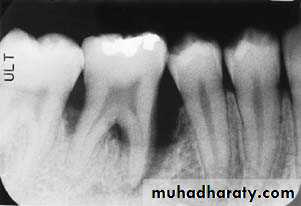

3.Furcation involvements:

Bone loss in the furcation area of the roots which is evidence of advanced disease in multirooted

teeth.

Initially seen as widening of the PL space at the crest of

the furcation . As lesion progresses, the bone

loss progresses apically.

Mild/moderate/sever.